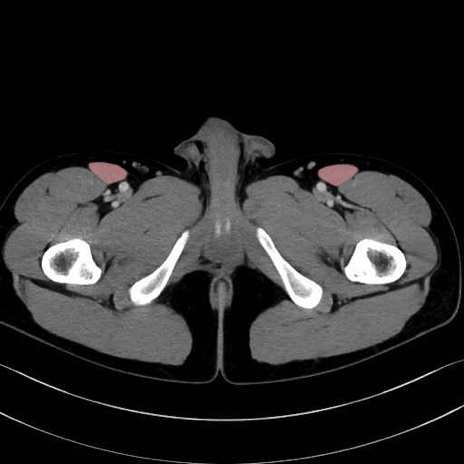

縫工筋 (Sartorius)